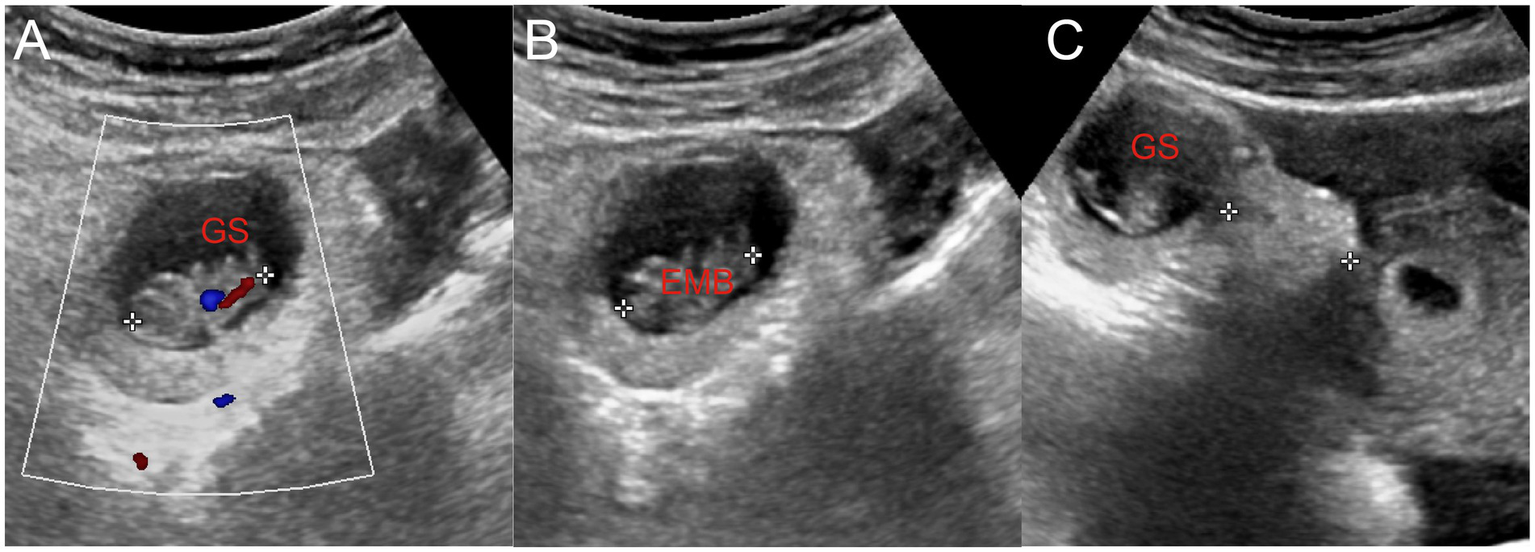

Figure 2

(A) Embryo in the gestational sac and primitive cardiac tube pulsation were observed. (B) The length of the embryo was approximately 2.1 cm. (C) Gestational sac located approximately 2.3 cm away from the uterus. GS, gestational sac; EMB, embryo.

Ultrasound showed no GS within the uterine cavity. A GS, measuring approximately 29 mm × 25 mm × 26 mm, was observed 23 mm above and slightly to the left of the uterus. The GS contained an echo of an embryo approximately 21 mm in length, suggesting a gestation of more than 8 weeks with a detectable fetal heartbeat. The ultrasound diagnosis was AP, pelvic and abdominal cavity effusion, pelvic hematoma formation, and uterine cavity effusion (Figures 1, 2). On the day of admission, blood tests revealed a human chorionic gonadotropin (hCG) level of 69,305 mIU/L. Blood routine tests indicated a hemoglobin level of 110 g/L, a white blood cell count of 14.67 × 109/L, and a rapid C-reactive protein level of < 0.5 mg/L.